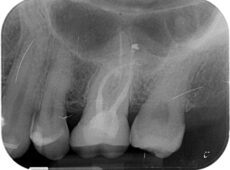

Controllo radiografica

Endodonzia

Attraverso questo trattamento, ci occupiamo della diagnosi e cura di patologie della polpa dentale e dei tessuti periapicali al fine di salvare e conservare i denti più compromessi.